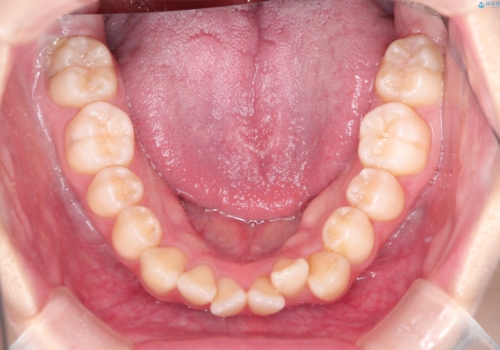

ワイヤーによる抜歯矯正でガタガタの改善

- 前歯のがたがたを主訴に来院されました。

上下の前歯が前方に傾斜しているのもあり、内側に前歯をひっこめるために上下左右の歯を1本ずつ抜歯して矯正することとしました。

ガタガタも改善しましたが、前歯が内側に引っ込むことにより口元もすっきりして、唇が閉じやすくなりました。